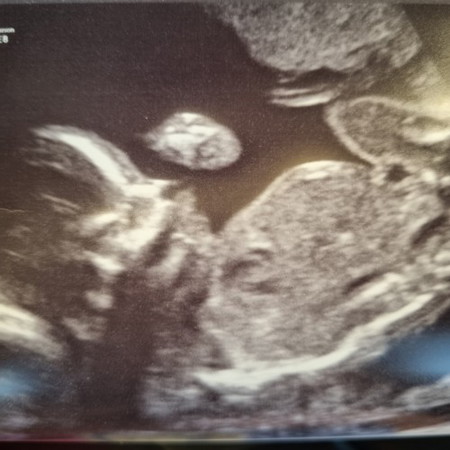

Week 21 detailed scan Detailed scan everything is good, baby growing well, all organs are fine, head down, placenta is high, weight 400g. Only downside is my BP is low, 81 ☹️